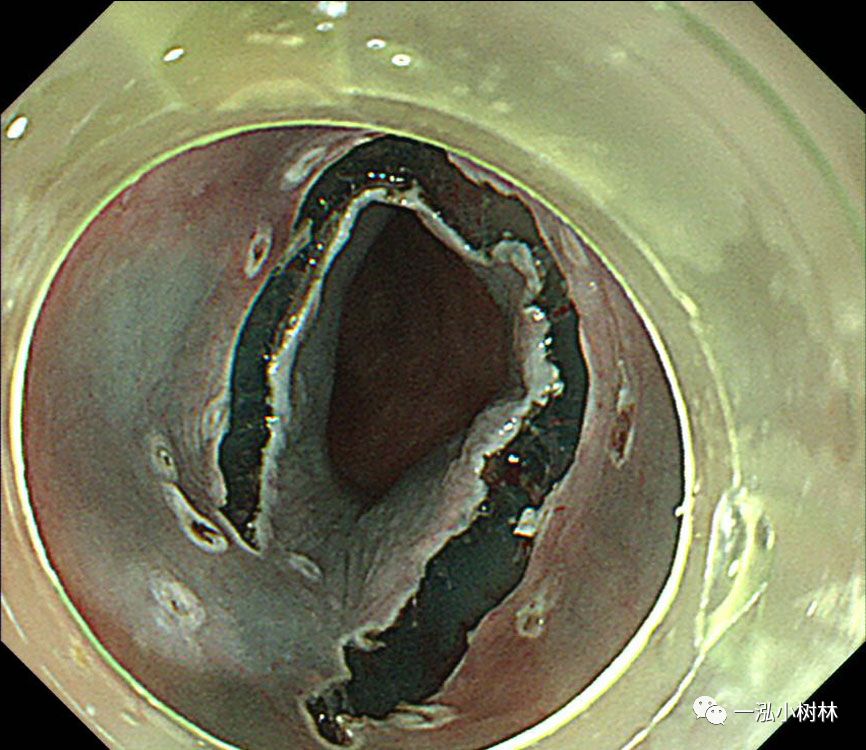

图10 牵引线从嘴中拉出以产生牵引力